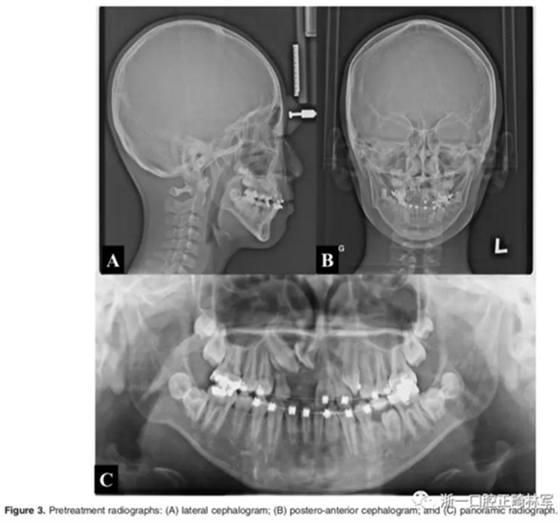

影像檢查:

全景X片及CBCT示:11-13復(fù)雜阻生,上頜前牙區(qū)牙槽骨水平不足;11阻生,遠(yuǎn)中旋轉(zhuǎn)90°,牙冠朝向腭側(cè),根尖位于鼻底、前鼻棘皮質(zhì)骨內(nèi),牙根形態(tài)彎曲;12、13不完全易位,12位置偏腭側(cè),13位置偏舌側(cè),12的牙根形態(tài)也較彎曲。

診斷:骨性I類,牙性II類,高角,多牙阻生,面部不對稱(右偏),上下切牙直立。